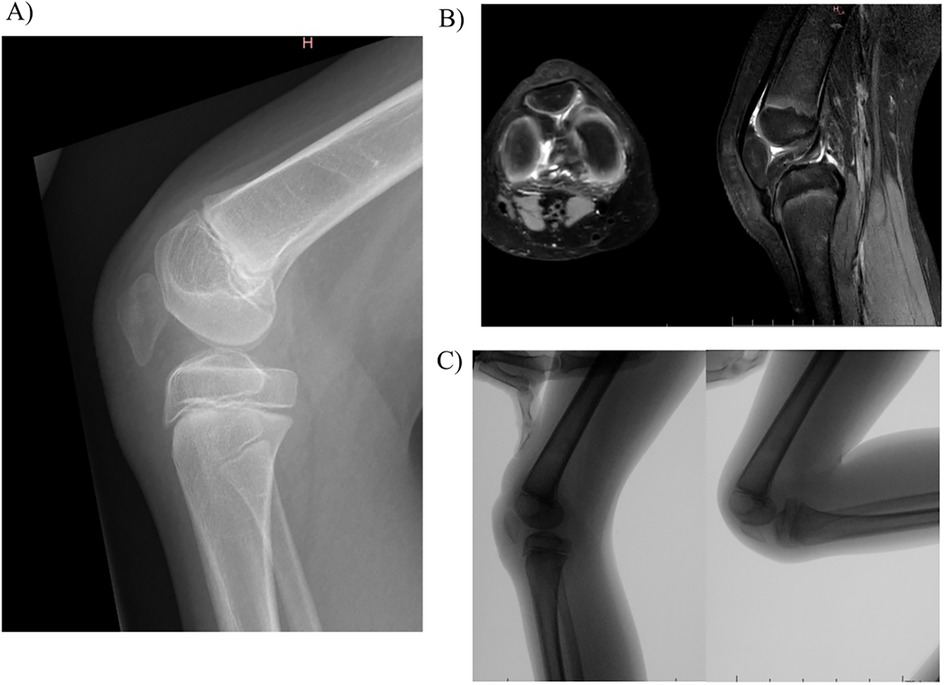

A ten-year-old girl was referred to our paediatric orthopaedics unit for aplasia of the right quadriceps accompanied by a persistent knee flexion deformity. The diagnosis had been made at the child's birth. She had initially been treated at another hospital, and she had undergone initial surgery at six years old. This consisted of an anterior distal femoral hemi-epiphysiodesis (with guided growth), which managed to restore complete knee extension. Over the following four years, the knee flexion deformity gradually returned, significantly hindering the walking process. Upon initial clinical examination, the anterior part of her thigh was observed to be severely atrophied, and the knee's flexion deformity was noted to have an extension defect of 40° but with no popliteal pterygium contracture. She was able to bend the knee to 120°. A conventional radiograph revealed an abnormally low-lying patella (Figure 1A), which appeared to be embedded in the femoral notch; it also showed a posterior static drawer due to a muscular disbalance between the knee flexors and extensors. However, no deformity of the distal femur or the proximal tibia was noted. Magnetic resonance imaging revealed that the patella was indeed stuck in the notch and that its shape had adapted to the local mechanical constraints (Figure 1B). The quadriceps muscle was severely aplastic, and although a quadricipital tendon was present, it was poorly developed and perpetuated proximally by a fibrous remnant. A dynamic radiological examination was carried out and demonstrated that passive extension was hindered by the position of the patella, which impinged between the femur and the tibia (Figure 1C).

Figure 1. Baseline evaluation of the knee: (A) conventional radiography; (B) magnetic resonance imaging; (C) dynamic radiological examination.